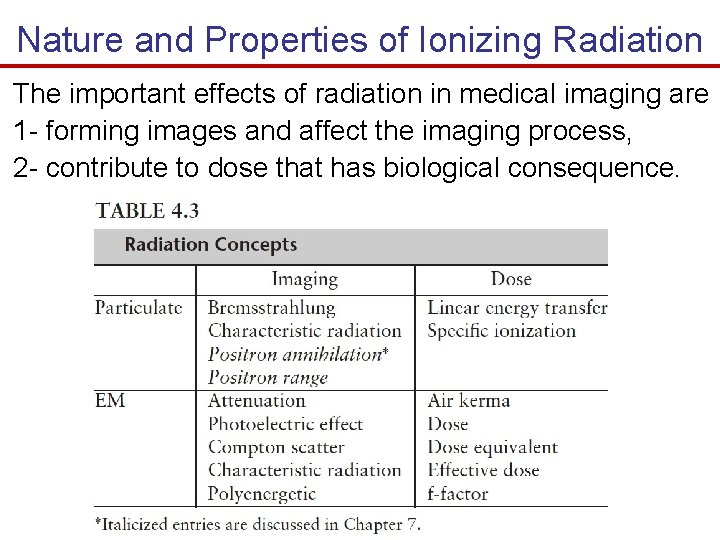

Nature and Properties of Ionizing Radiation The important effects of radiation in medical imaging are 1 - forming images and affect the imaging process, 2 - contribute to dose that has biological consequence.